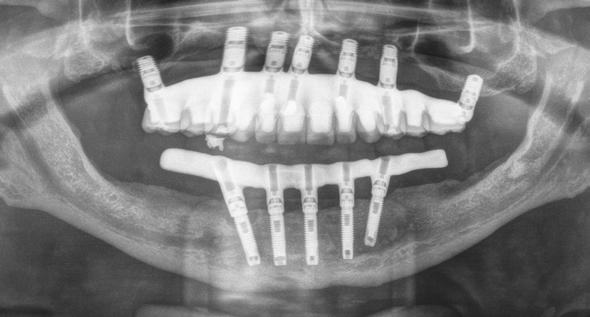

En el maxilar superior, existen trabajos de revisión donde se pone de manifiesto que los implantes cortos y extracortos tienen también un correcto comportamiento biomecánico y pérdidas óseas similares a los implantes de mayor longitud, por lo que para esta área anatómica también son una opción de tratamiento predecible.1,12 En la siguiente serie de casos clínicos, presentamos 5 pacientes en los que se han realizado rehabilitaciones sobre implantes extracortos 5.5 mm para generar prótesis de arco completo, en maxilar y mandíbula y su seguimiento a lo largo del tiempo observándose la supervivencia de los implantes, la pérdida ósea crestal con la función y las posibles complicaciones protésicas acontecidas durante el tiempo de seguimiento.

Figura 1. Diámetros y longitudes incluidos en el estudio según su posición.

Figura 2 y 3. Figuras intraorales del paciente de 67 años que acude a la consulta para rehabilitación sobre implantes superior, portador de una prótesis completa removible con una atrofia ósea evidente al ser la prótesis retirada. Figura 4. La radiografía inicial muestra una atrofia marcada en sentido vertical, que debe ser constatada posteriormente mediante un TAC así como para la planificación de la colocación de los implantes. Figura 5 y 6. Encerado diagnóstico para comenzar la planificación de la colocación de los implantes superiores guiados por la posición ideal que deben tener los dientes en la prótesis. De este encerado se realiza una guía radiológica que nos permita trasladar estas posiciones al TAC de planificación.

Fueron reclutados 6 pacientes en los que se colocaron 30 implantes para realizar rehabilitaciones completas. La edad media de los pacientes incluidos en el estudio fue de 66.75 años (+/- 5,16) y un 86.7% fueron mujeres. El 63.3% de los implantes se insertaron en el maxilar superior y el 36.7% restante en la mandíbula, formando parte de 4 rehabilitaciones

completas superiores y 3 inferiores. Todos los implantes presentaron una longitud de 5.5 m m, con diámetros comprendidos entre los 2.5 y los 5.5 mm. Las posiciones de los implantes corresponden a distribuciones biomecánicas para la realización de prótesis completas tanto en el maxilar como mandíbula (incisivos, premolares y molares). Los diámetros y longitudes de los implantes incluidos en el estudio en función de

181. Septiembre 2023 51 Rehabilitaciones completas implantosoportadas

su posición se muestran en la Figura 1.

Figura 7­9. Cortes de planificación del cone beam donde observamos la extrema atrofia vertical y la posición en la que deberían situarse los dientes con una gran discrepancia entre esta posición y la base ósea. Vemos también como se planifican implantes extracortos de 5.5 mm de longitud en todas las localizaciones. Figura 10. Radiografía panorámica tras la colocación de los implantes.

En las Figuras 2­17 se puede observar uno de los casos incluidos en el estudio.

Figura 11­12. Prueba del encerado para la realización de la prótesis provisional tras 6 meses desde la colocación de los implantes. Figura 13. Radiografía panorámica tras la colocación de prótesis provisional de carga progresiva. Figura 14 y 15. Planificación por CAD/CAM de la estructura de la prótesis definitiva y finalización de la misma con el cementado de coronas de disilicato sobre la estructura.